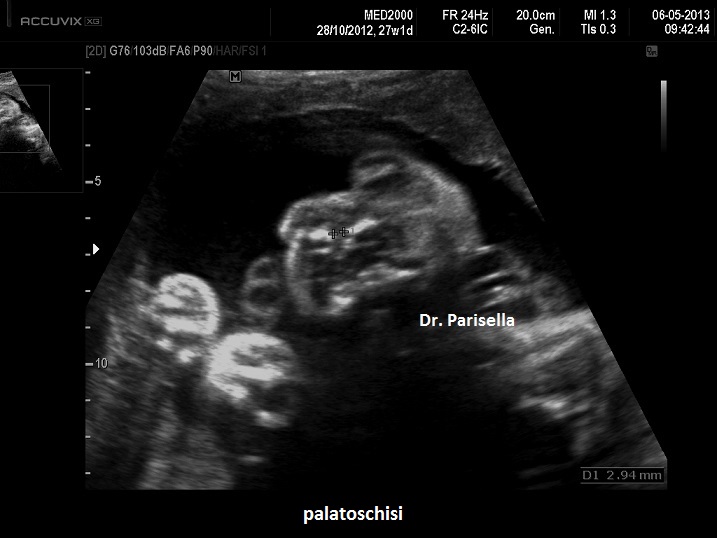

E' una malattia genetica rara caratterizzata da lussazione congenita poliarticolare tra cui il Congenital Genu Recurvatum (bilaterale), piede torto, mano torta e caratteristica facies caratterizzata da ipertelorismo, radice del naso depressa, bozza frontale prominente, micrognazia e palatoschisi.